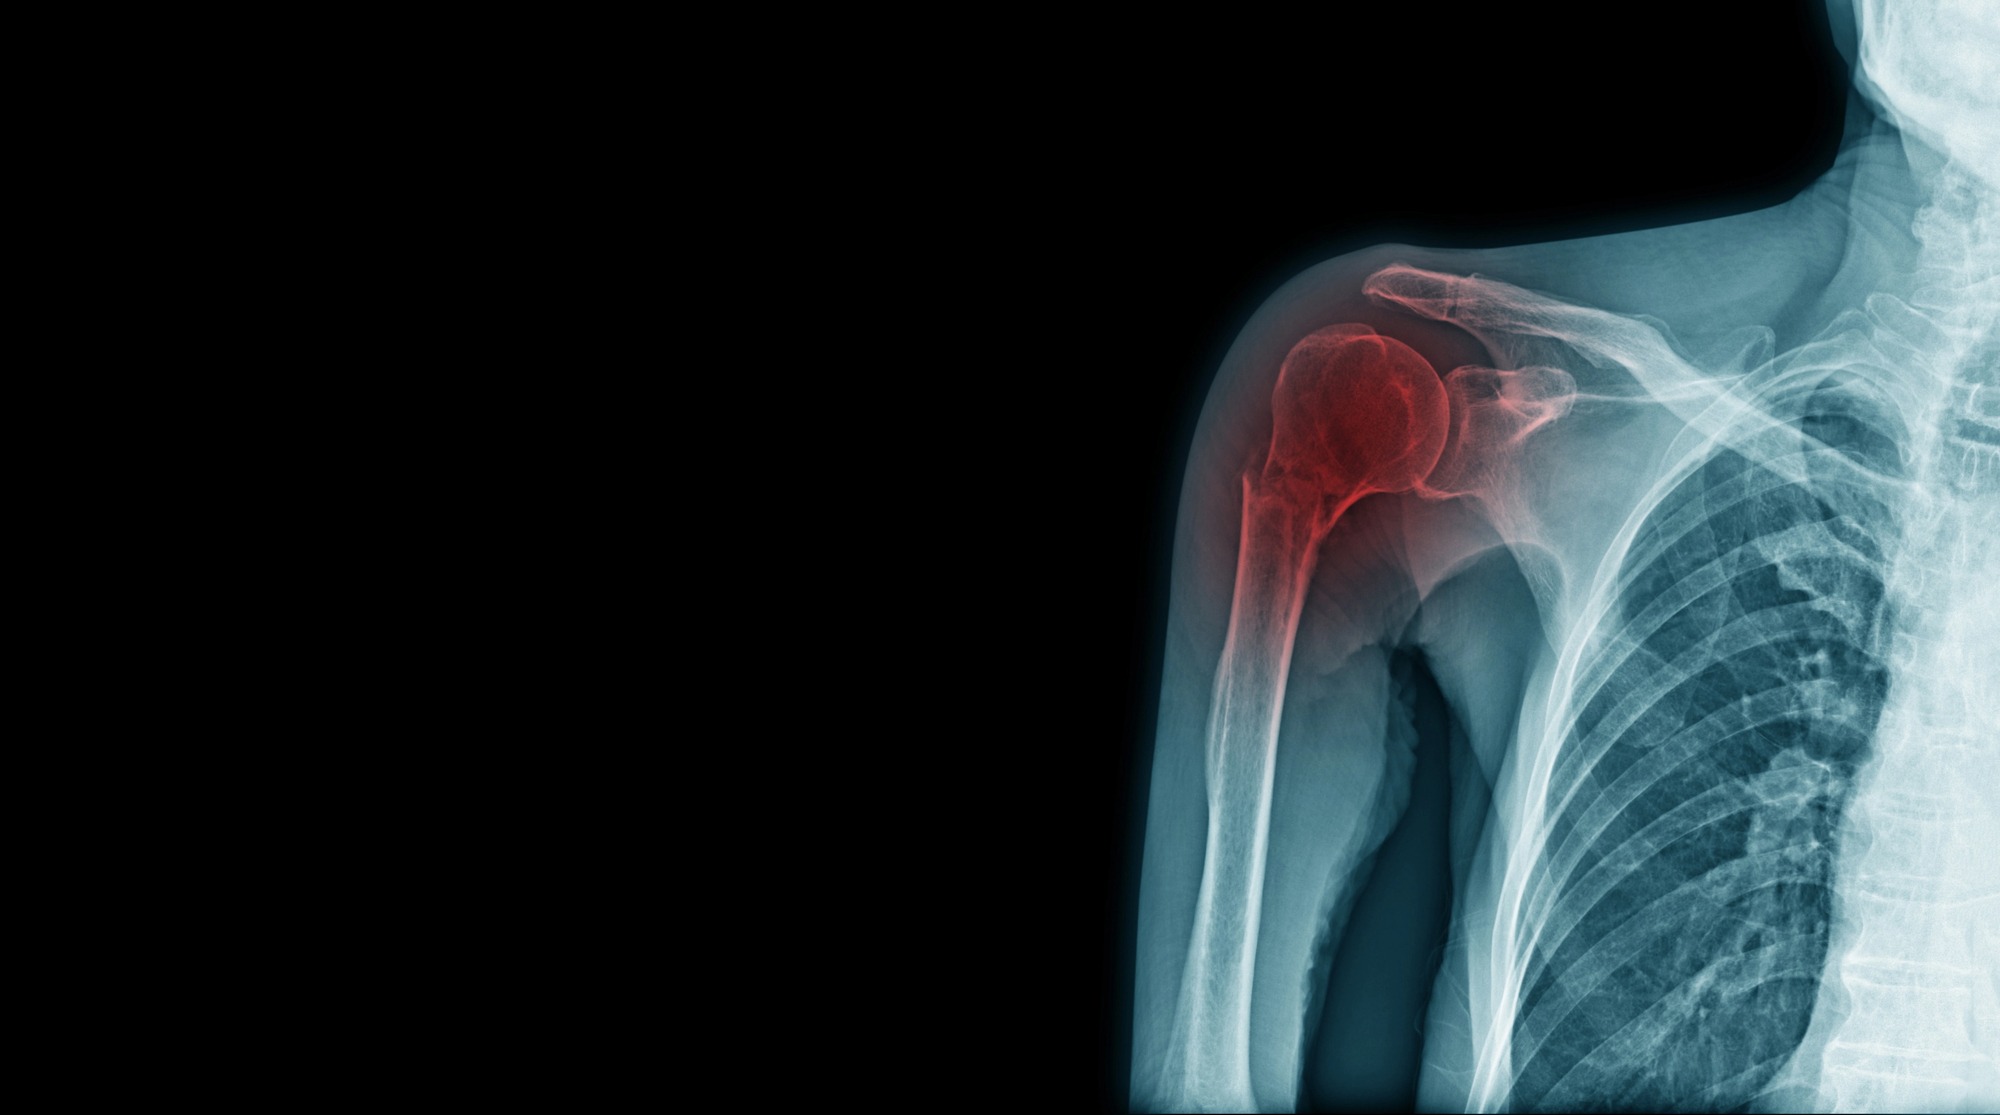

Accurate diagnosis is essential for effective treatment. Healthcare providers typically begin with a comprehensive evaluation that includes a physical examination and a review of the patient’s medical history. Imaging techniques such as X-rays, MRI scans, or ultrasound may be used to assess the extent of the injury or condition.